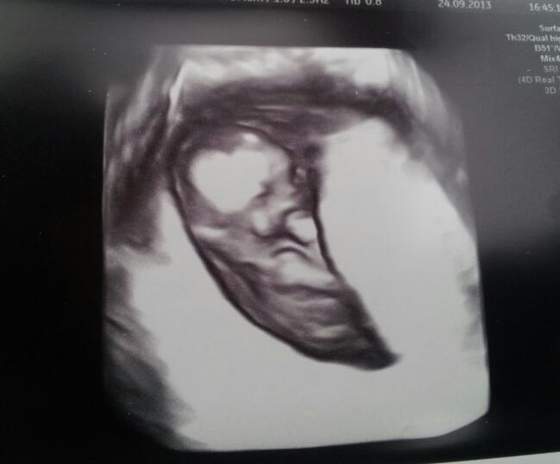

Gratuluję dziewczyny udanych wizyt. Ja po wczorajszej wizycie wróciłam do domu mega szczęśliwa i w końcu zaczęłam się cieszyć że jestem w ciąży. Przezierność karku w porządku, serducho bije jak dzwon, więc na chwilę obecną wszystko jest ok. Dzidzia wyjątkowo spokojna była tylko (jak to powiedział lekarz) chyba miała czkawkę. Mam już nie brać kwasu foliowego. Wyniki krwi bardzo dobre więc nie ma potrzeby brania witamin. Kolejna wizyta za 3 tygodnie, a za 7 tygodni kolejne USG tym razem połówkowe.

A oto dzidzia